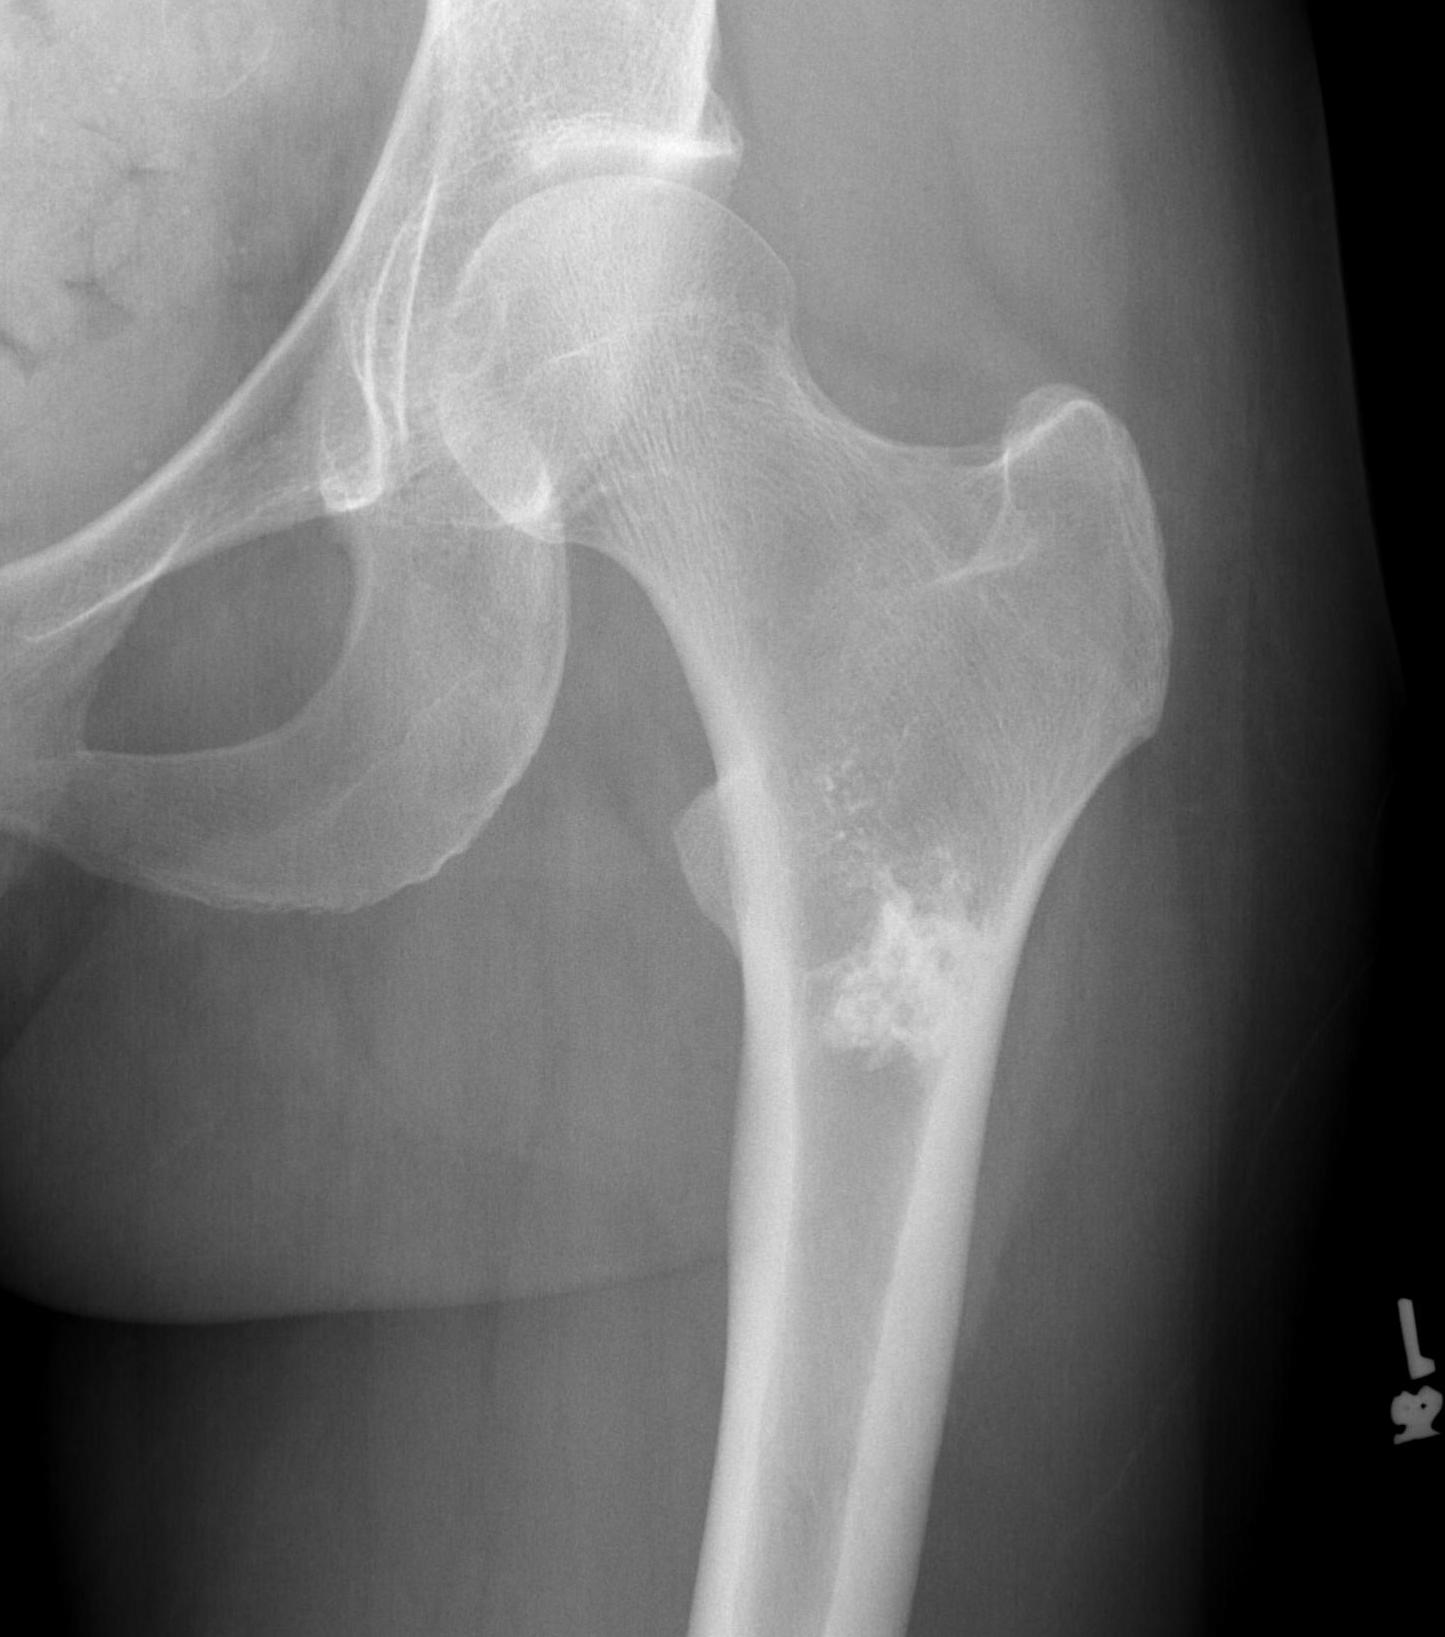

Enchondroma

Benign intramedullary cartilage lesion